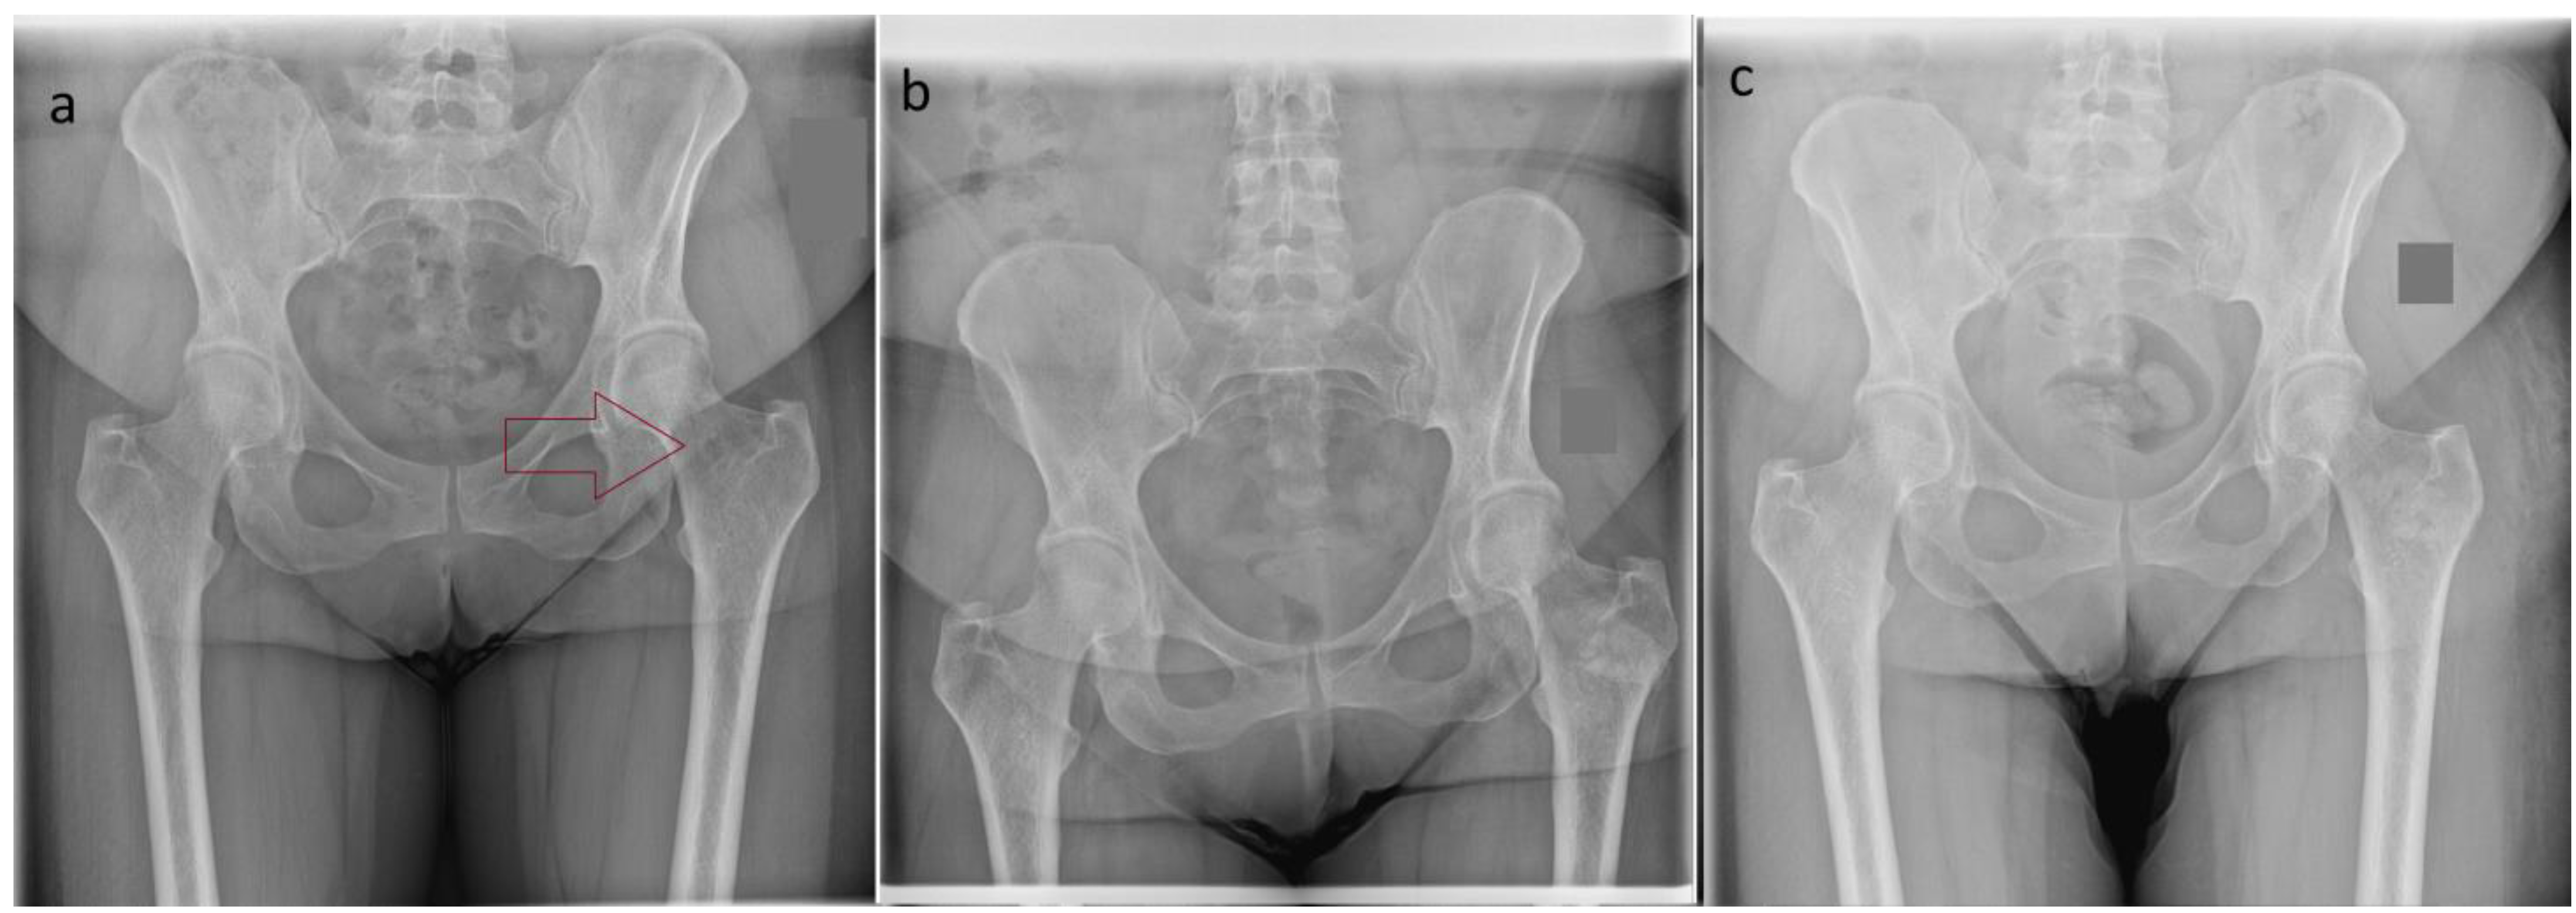

| 4 | F | 48 | Ilium | 25 | Enchindroma |

| 4 | Score I | 7 | 4 | None |